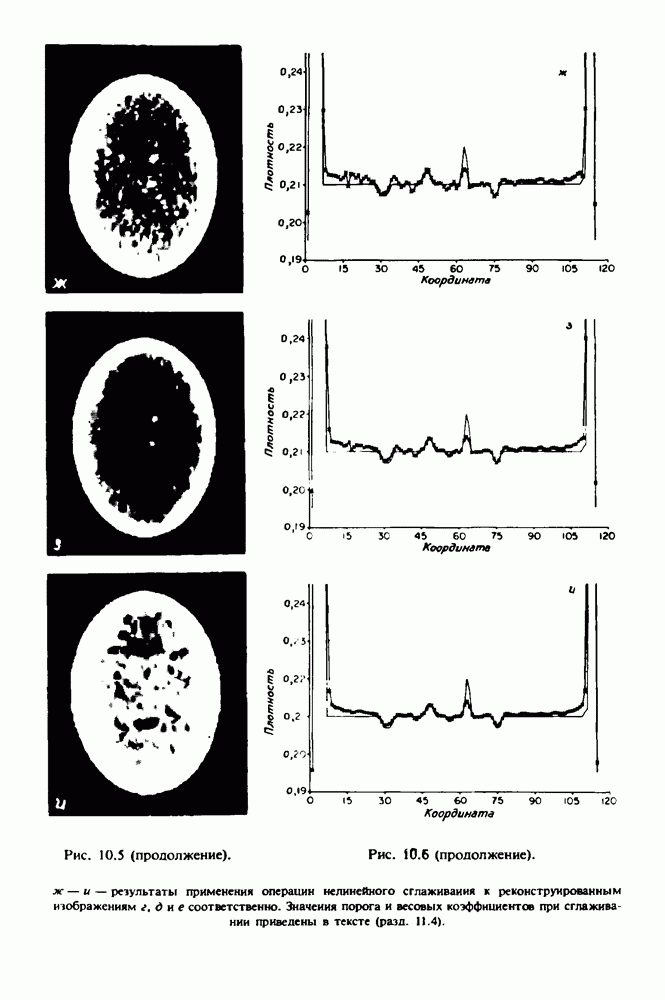

15.5. ЭКСПЕРИМЕНТАЛЬНЫЕ РЕЗУЛЬТАТЫ

Наш первый пример относится к случаю отображения системы желудочков головного мозга человека, которое было сделано по восьми смежным срезам толщиной На рис. 15.1 (вверху) приведены фрагменты из 80 х 80 элементов изображения трех из указанных срезов. Система желудочков изображена на фрагментах полностью. Размер элемента изображения в срезах составлял 1,5 х 1,5 мм, что соответствовало размеру элементарного

объема 1,5 х 1,5 х 8 мм, хотя более желательна, как и в предыдущих разделах, была бы кубическая форма элементарных объемов. Чтобы преобразовать элементарные объемы в кубические, использовалась линейная интерполяция данных для оценки 38 смежных срезов толщиной 1,5 мм. Таким образом, формируется массив из 80 х 80 х 32 чисел, характеризующих среднюю плотность множества элементарных объемов кубической формы.

Причина, по которой желудочки мозга выглядят более темными, чем окружающие ткани, состоит в том, что они содержат спинномозговую жидкость с несколько меньшим, чем у мозга, линейным коэффициентом ослабления (табл. 4.1). Поэтому диапазон значений, введенный в разд. 15.1, оказался таким, что его верхний предел стал больше, чем линейный коэффициент ослабления цереброспинальной жидкости, но меньшим, чем для самого мозга. Последнее означает, что все элементарные объемы, характеризующие спинномозговую жидкость, имеют числа Хаунсфилда в указанном диапазоне Таким образом, множество элементарных объемов, в которых числа Хаунсфилда лежат в диапазоне (разд. 15.2), содержит не только области желудочков, но также и другие части мозга, либо заполненные спинномозговой жидкостью, либо не заполненные ей, но имеющие по разным причинам такие же числа Хаунсфилда в данном диапазоне, например, вследствие наличия шума в исходных данных, артефактов при реконструкции и т.д. Элементарные объемы, которые принадлежат множеству изображены в виде светлых областей в нижней части рис. 15.1. Анатомическая картина соответствующих частей системы желудочков, показывающая в том числе положение corpora quadragemina («четверохолмие»), приведена на рис. 15.6.

Рис. 15.6. Анатомическая структура фрагмента системы желудочков головного мозга человека. 1 — передние рога латерального желудочка; 2 — третий желудочек; 3 — четверохолмие; 4 — задние рога латерального желудочка.